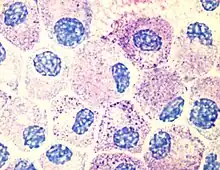

Photo of cultured mast cells at 100X stained with Tol Blue

One of the most outstanding results of his dissertation investigations was the discovery of a new cell type. Ehrlich discovered in the protoplasm of supposed plasma cells a granulate which could be made visible with the help of an alkaline dye. He thought this granulate was a sign of good nourishment, and accordingly named these cells mast cells, (from the German word for an animal-fattening feed, Mast). This focus on chemistry was unusual for a medical dissertation. In it, Ehrlich presented the entire spectrum of known staining techniques and the chemistry of the pigments employed. While he was at the Charité, Ehrlich elaborated upon the differentiation of white blood cells according to their different granules. A precondition was a dry specimen technique, which he also developed. A drop of blood placed between two glass slides and heated over a Bunsen burner fixed the blood cells while still allowing them to be stained. Ehrlich used both alkaline and acid dyes, and also created new "neutral" dyes. For the first time this made it possible to differentiate the lymphocytes among the leucocytes (white blood cells). By studying their granulation he could distinguish between nongranular lymphocytes, mono- and poly-nuclear leucocytes, eosinophil granulocytes, and mast cells.